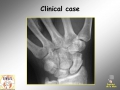

Scaphoid fracture